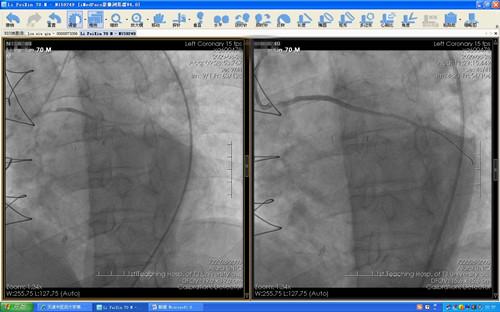

经心血管科团队积极评估、充分准备后,于住院第4天(8月28日)在介入中心团队配合下顺利完成原位血管及桥血管造影,分别于原位血管及一支桥血管植入支架,心肌灌注明显改善,患者胸痛未再发作,生活质量明显好转。

图  原位血管及桥血管介入前后造影结果